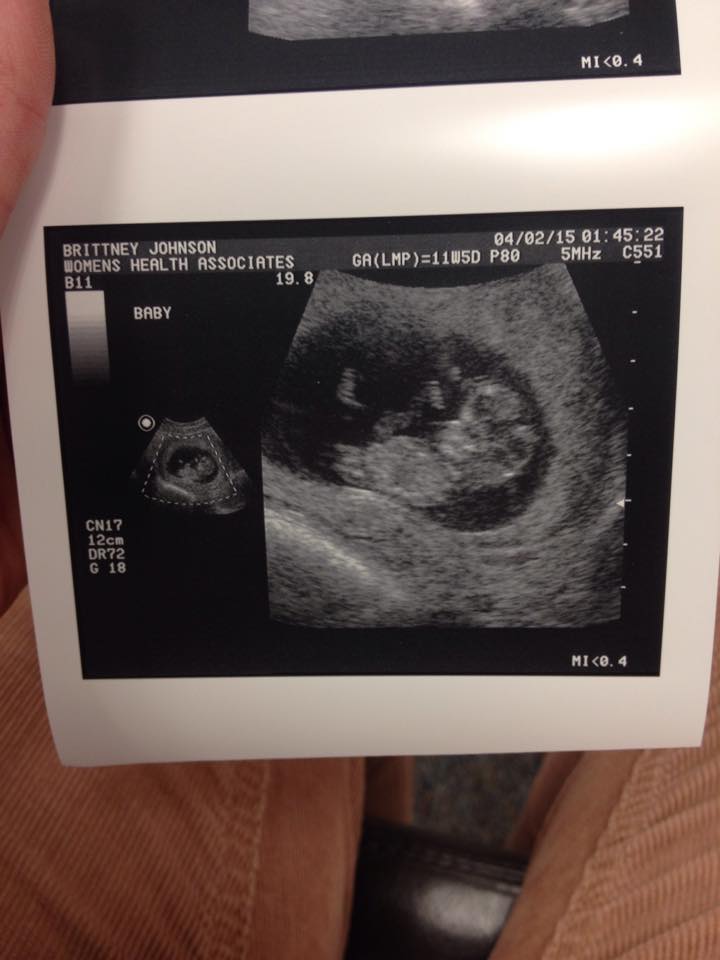

Here's our little love at 12 weeks! I can't get over how much he/she already looks like a 'real' person, can't wait for the next US when we find out the sex! So excited